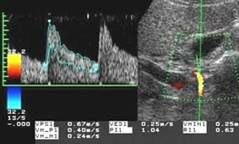

Определение количественных показателей гемодинамики печени. Больной исследуется в положении лежа на левом боку. Сканирование проводится из доступа через межреберные промежутки (интеркостальный доступ) или из правого подреберья (субкостальный доступ) в зависимости от оптимальной видимости исследуемого сосуда и его хода по отношению к углу инсонации. Задержка дыхания производится больным вне фазы глубокого вдоха или выдоха, что снижает влияние фаз дыхания на характер кровотока в исследуемых сосудах. При определении скоростей кровотока сканирование проводится таким образом, чтобы направление распространения ультразвуковых волн максимально совпадало с продольным ходом сосуда и не превышало 60 градусов по отношению к нему. Величина пробного объема, помещаемого в середину просвета сосуда, составляет приблизительно одну его треть. При измерении таких уголнезависимых величин, как индекс резистентности (RI) и пульсационный индекс (PI), коррекция угла инсонации имеет меньшее значение. При исследовании кровотока во внутрипеченочной части основного ствола воротной вены Nishihara (1994) отметил наилучшие результаты при сканировании из межреберного доступа. Он помещал контрольный объем в основной ствол воротной вены за 1-2 см до ее бифуркации на левую и правую долевые ветви. С учетом данных литературы и своего личного опыта мы считаем указанную выше позицию оптимальной для определения скоростных показателей воротного кровотока (см. рис.).

В норме воротный кровоток имеет типичный венозный спектр, зависящий от фаз дыхания и располагающийся над базовой линией, что соответствует его обычному (гепатопетальному) направлению. Исследование скоростных показателей в основном стволе печеночной артерии проводится в области вертикально направленной части, в точке, наиболее удаленной от бифуркации чревного ствола при сканировании из правого подреберья. В норме скорость кровотока в ней не превышает 60-70 см/сек, RI обычно равен 0,65-0,7.